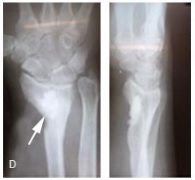

El quiste óseo aneurismático fue descrito como una lesión hemorrágica que contiene cavidades quísticas, de paredes delgadas, llenas de sangre, localmente destructivo y no se considerada una neoplasia verdadera. Este artículo presenta un paciente masculino, con quiste óseo aneurismático en la cadera. Ver más…